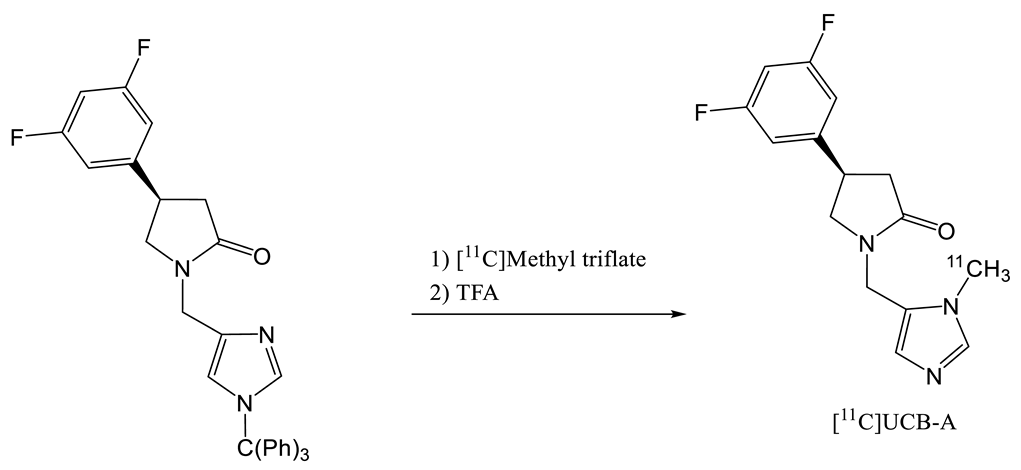

- Estrada, S.; Lubberink, M.; Thibblin, A.; Sprycha, M.; Buchanan, T.; Mestdagh, N.; Kenda, B.; Mercier, J.; Provins, L.; Gillard, M.; et al. [11c]Ucb-a, a Novel Pet Tracer for Synaptic Vesicle Protein 2a. Nucl. Med. Biol. 2016, 43, 325–332. [Google Scholar] [CrossRef] [PubMed]

| 4 | [18F]UCB-A | [23] |  | 7.9 [24] | ND a | 65 | 14 (dc) |